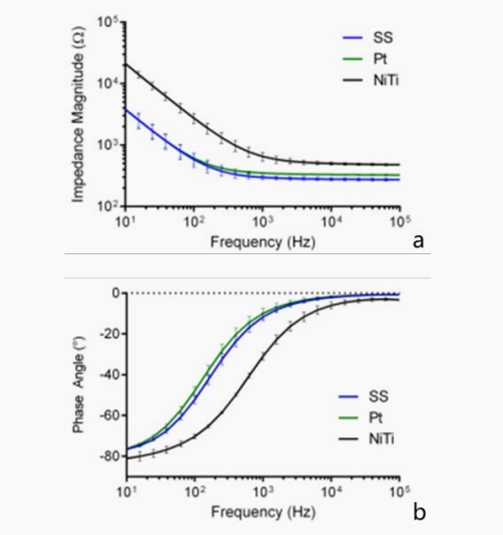

许多研究使用了美敦力公司的自扩张NiTi血管内支架。使用经紫外线固化的生物相容性粘合剂将8-12个Pt电极固定在支架上。用聚酰亚胺绝缘的Pt-W线传输电信号,用激光焊接将Pt-W线连接到Pt电极上。一根直径为410 μm的不锈钢导丝,作为核心棒,便于支架植入血管。Pt-W线缠绕在铁芯棒上,并延伸到外部设备上。形态结构和三维建模如图3所示。

图 3 NiTi支架电极的(a)三维建模 (b) NiTi支架扩张(c)聚合物支架的物理形态